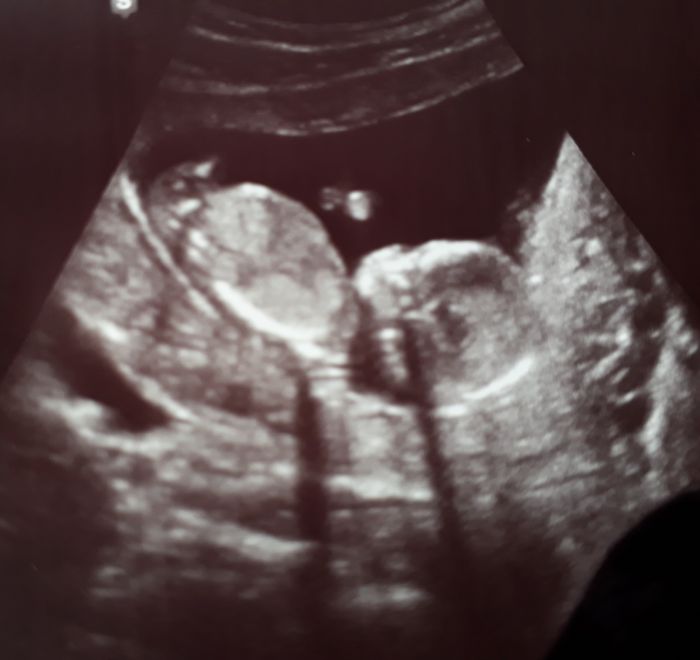

Ahoj holky , dlouho jsem tu nebyla..... Screening jsem mela cca před 3 týdny. Vse v pořádku

a s největší pravděpodobností to bude chlapeček

Ahoj holky,dnes screening 13+5,miminko je zdrave

Pan doktor mi rekl,ze si mam pohlavi zjistit sama,ze ho nikomu nerika.Zajel mezi nozky a rika"Tady ma jedno,tady ma druhy a neni to pupecnik".Takze asi cekame chlapecka?

Tak už i my jsme konečně po screeningu. Morfologicky všechno vypadalo dobře, výsledky genetiky budou večer. Nakonec je všechno trochu jinak, než jsme čekali - prcci mají společnou placentu, takže jsou to jednovaječná mo-bi dvojčátka. Bohužel je tím všechno komplikovanější, nezbývá než doufat, že placenta vydrží až do 36. týdne, kdy je nejzazší termín porodu. Moc jsem se těšila na holčičku, když už doma jednoho kluka máme, ale vypadá to na čistě mužskou smečku :)